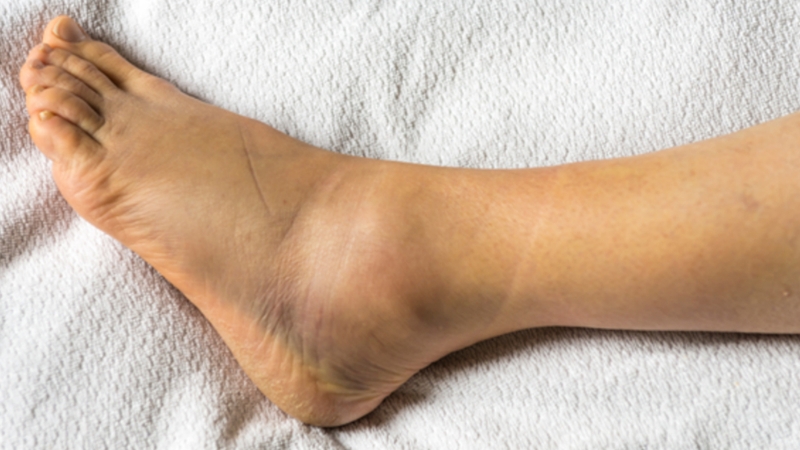

Các dấu hiệu phổ biến của rạn xương cổ chân bao gồm sưng, đau nhức, và bầm tím ở vùng tổn thương làm khả năng vận động của cổ chân bị hạn chế.

Để chẩn đoán và định hướng điều trị, bác sĩ thường sẽ yêu cầu các kỹ thuật hình ảnh như chụp X-quang, CT-scan, MRI,... Trong số đó, chụp X-quang thường được sử dụng phổ biến nhất vì tính đơn giản và chi phí thấp. Nó giúp bác sĩ xác định vị trí rạn của xương, từ đó đưa ra phương hướng điều trị phù hợp.